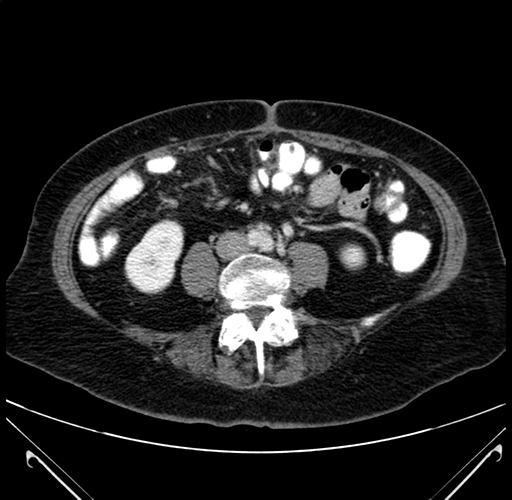

Pre-Chemo: Axial Venous

Axial Venous